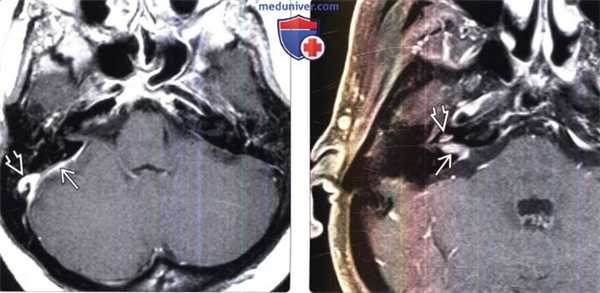

(Слева) МРТ, постконтрастное Т1-ВИ, аксиальный срез: метастазы рака легкого в твердую мозговую оболочку в области ММУ. Необходимо различать контрастируемую утолщенную твердую мозговую оболочку от нормального участка контрастирования сигмовидного синуса. При исследовании СМЖ были выявлены злокачественные клетки.

(Справа) МРТ, постконтрастное Т1-ВИ, режим подавления сигнала от жира, аксиальный срез: в правом ВСПВ определяется контрастируемый метастаз, распространяющийся через канал улиткового нерва и стержень улитки в перепончатый лабиринт.

(Слева) МРТ, постконтрастное Т1-ВИ, корональный срез: в клочке правого полушария мозжечка определяется контрастируемый метастаз карциномы молочной железы. Обратите внимание на нормальный клочок и сосудистое сплетение цистерны

(Справа) МРТ, FLAIR, аксиальный срез: у этого же пациента определяется, что объемное образование несколько гипоинтенсивнее прилегающего серого вещества мозга. Вазогенный отек вещества средней ножки и самого мозжечка визуализируется как гиперинтенсивная область. Левый клочок в норме.

(Слева) МРТ, постконтрастное Т1-ВИ, режим подавления сигнала от жира, аксиальный срез: у пациента с верифицированными отдаленными метастазами рака прямой кишки определяется контрастирование метастаза, в сосудистом сплетении нижней части цистерны ММУ и отверстия Люшки. Также визуализируется нормальное сосудистое сплетение справа.

(Справа) МРТ, постконтрастное Т1 -ВИ, режим подавления сигнала от жира, аксиальный срез: с двух сторон в областях ММУ-ВСП определяются «падающие» метастазы супратенториальной мультиформной глиобластомы. Наряду с двусторонними контрастируемыми метастазами во ВСП, на поверхности мозжечка выявляются множественные лептоменингиальные метастазы.